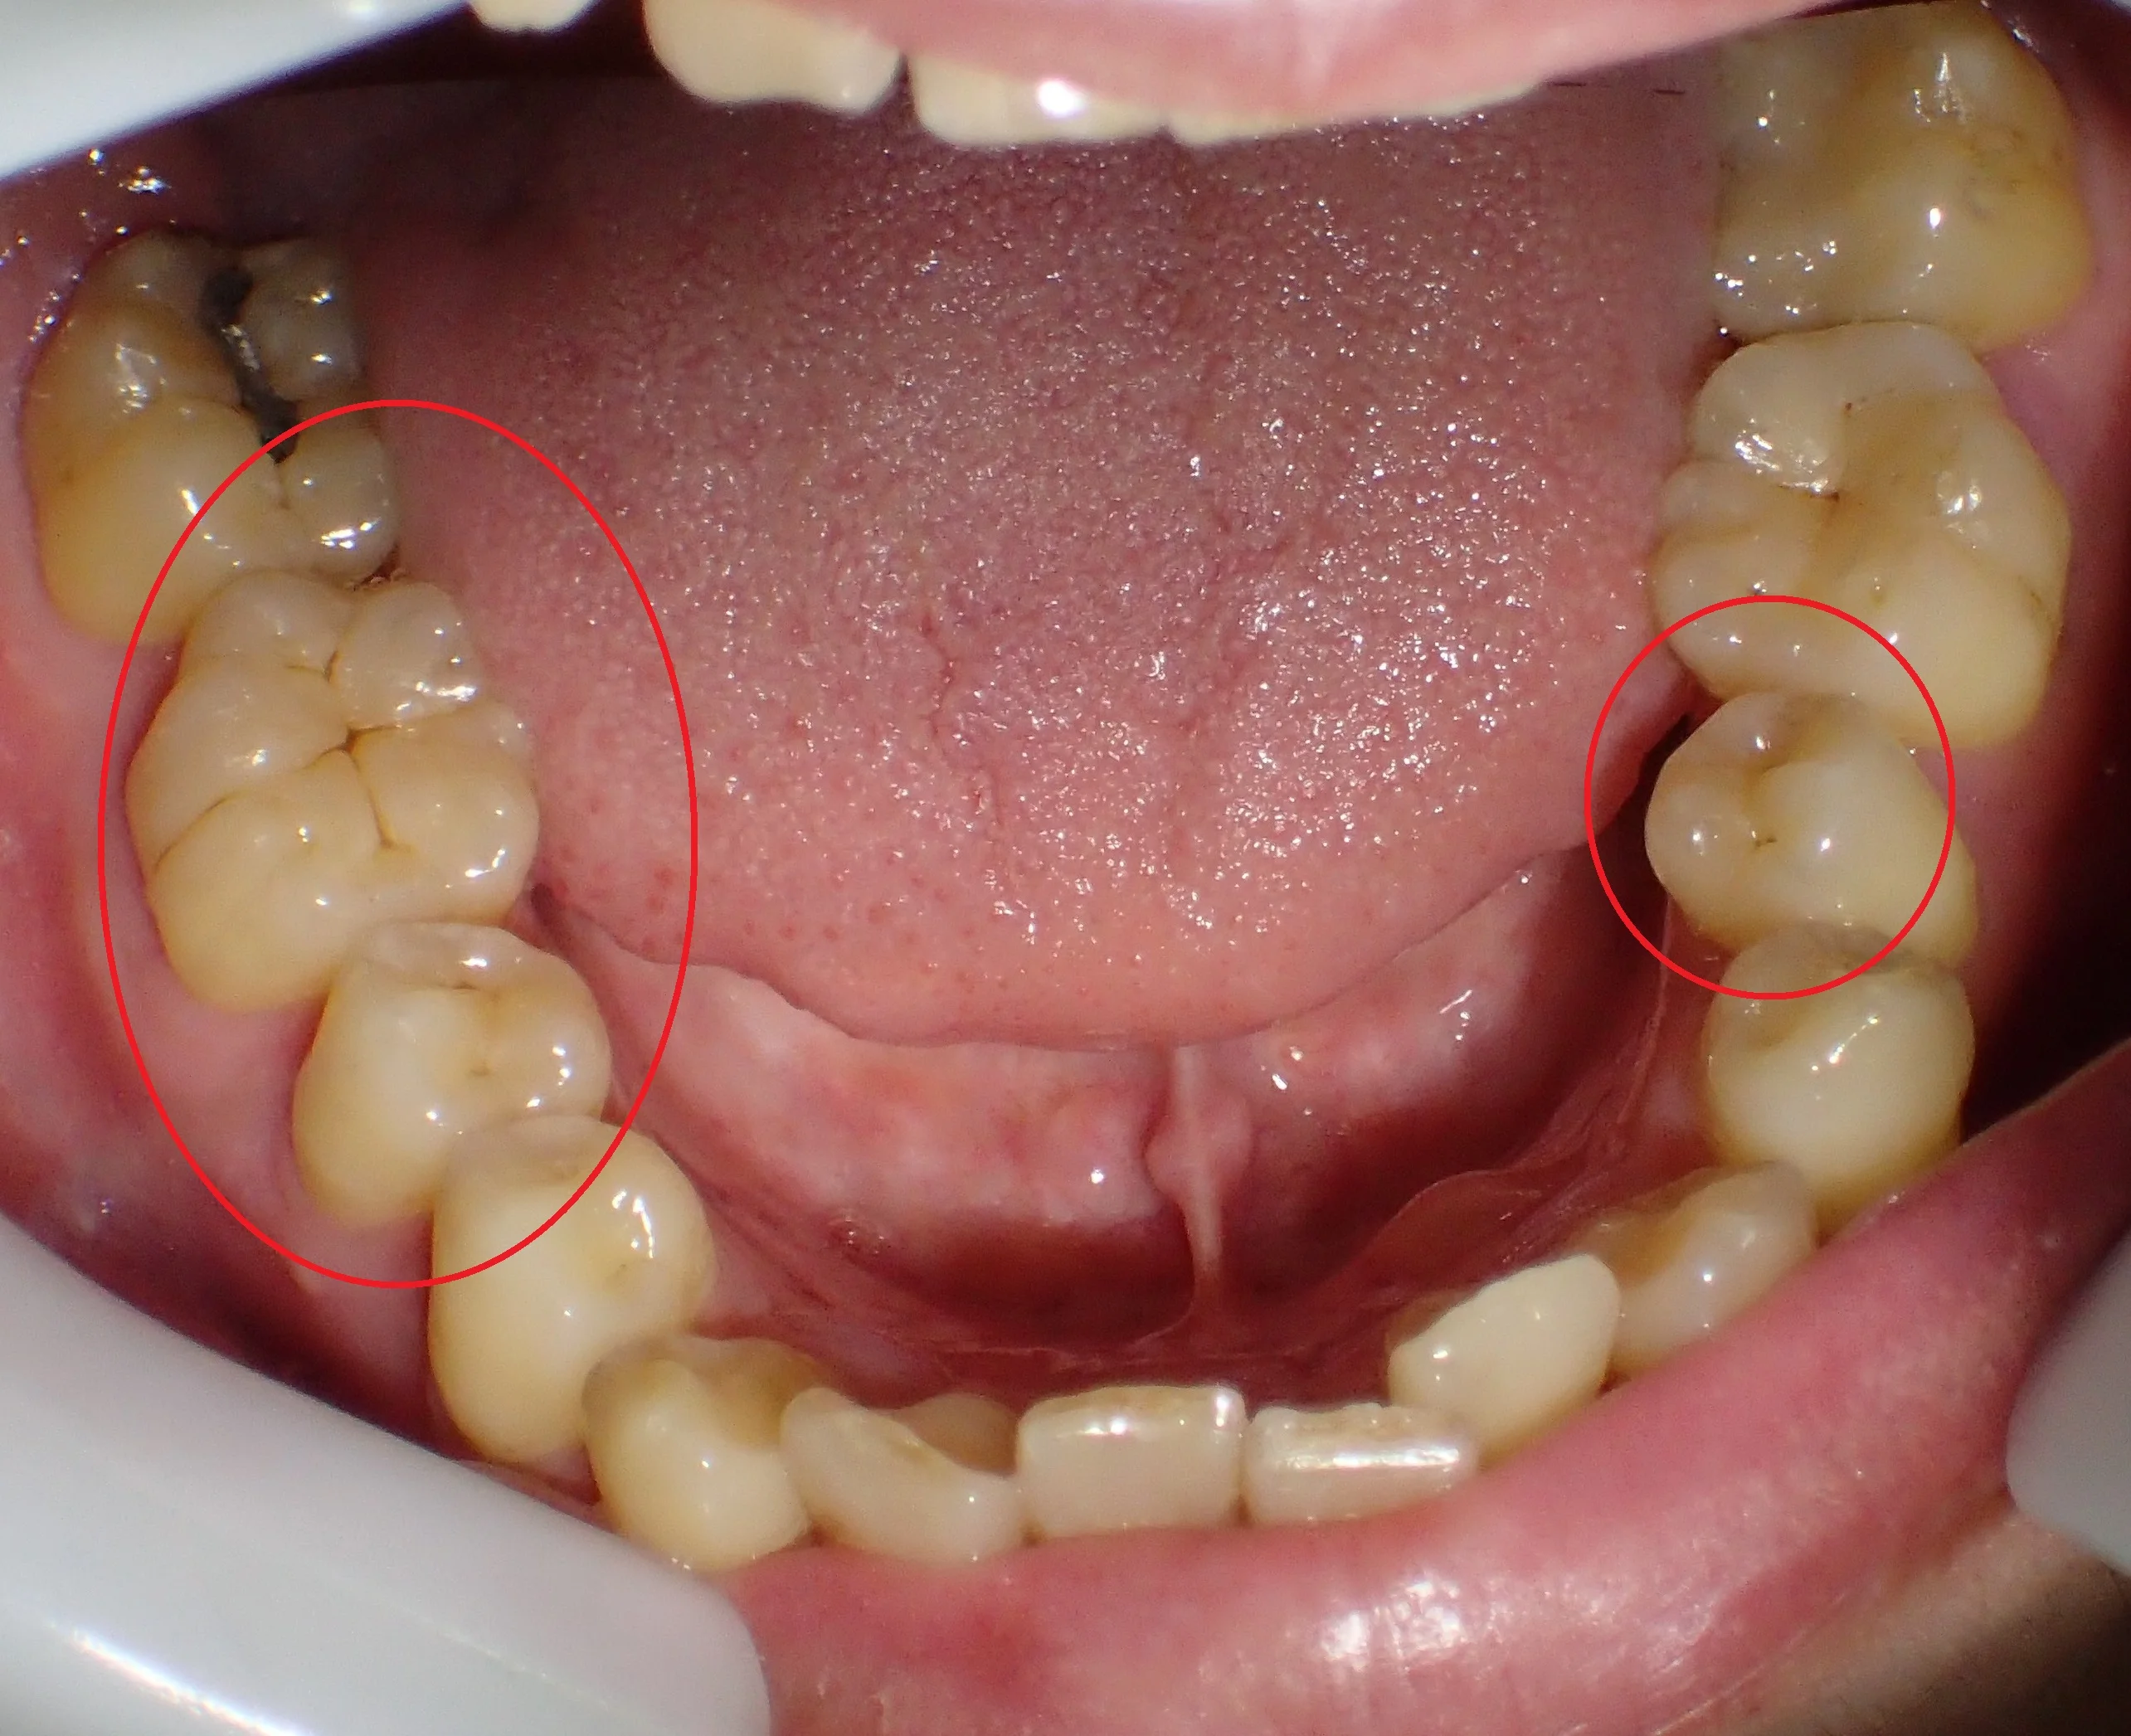

まだ坂寄歯科医院には全顎的にダイレクトボンディングで治療した症例がありませんので、前の医院にて治療を完了された方の写真を載せたいと思います。

どこを治療したかわかりますか?

答えは下の方に書いておきますので、スクロールしてください。

治療した箇所は、

・右下5,6

・左下5

でした!

治療した部位は全て元々詰めていたメタルインレーが再び虫歯になってしまった状態でした。

幸いあまり大きくは削られてはいなかったので、全てをダイレクトボンディングで治療することが出来ました。

右下7はアマルガムという金属が入っていますが、別にそこは虫歯にはっていなかったです。

なので、患者さんの同意の下、治療はせずにそのままにしています。

ステイニングを行って、歯の溝の部分に色を付けると歯に立体感が出るので、急激に天然の歯っぽくなりますよね!

ちなみに、この方、右下6を一番最初に治させて頂いたのですが・・・

もう少しステイニングを弱めにしてほしいとの要望があり、他の箇所は控えめなステイニングにしました。

全ての治療を終え、患者さん本人には非常に喜んでもらえました。